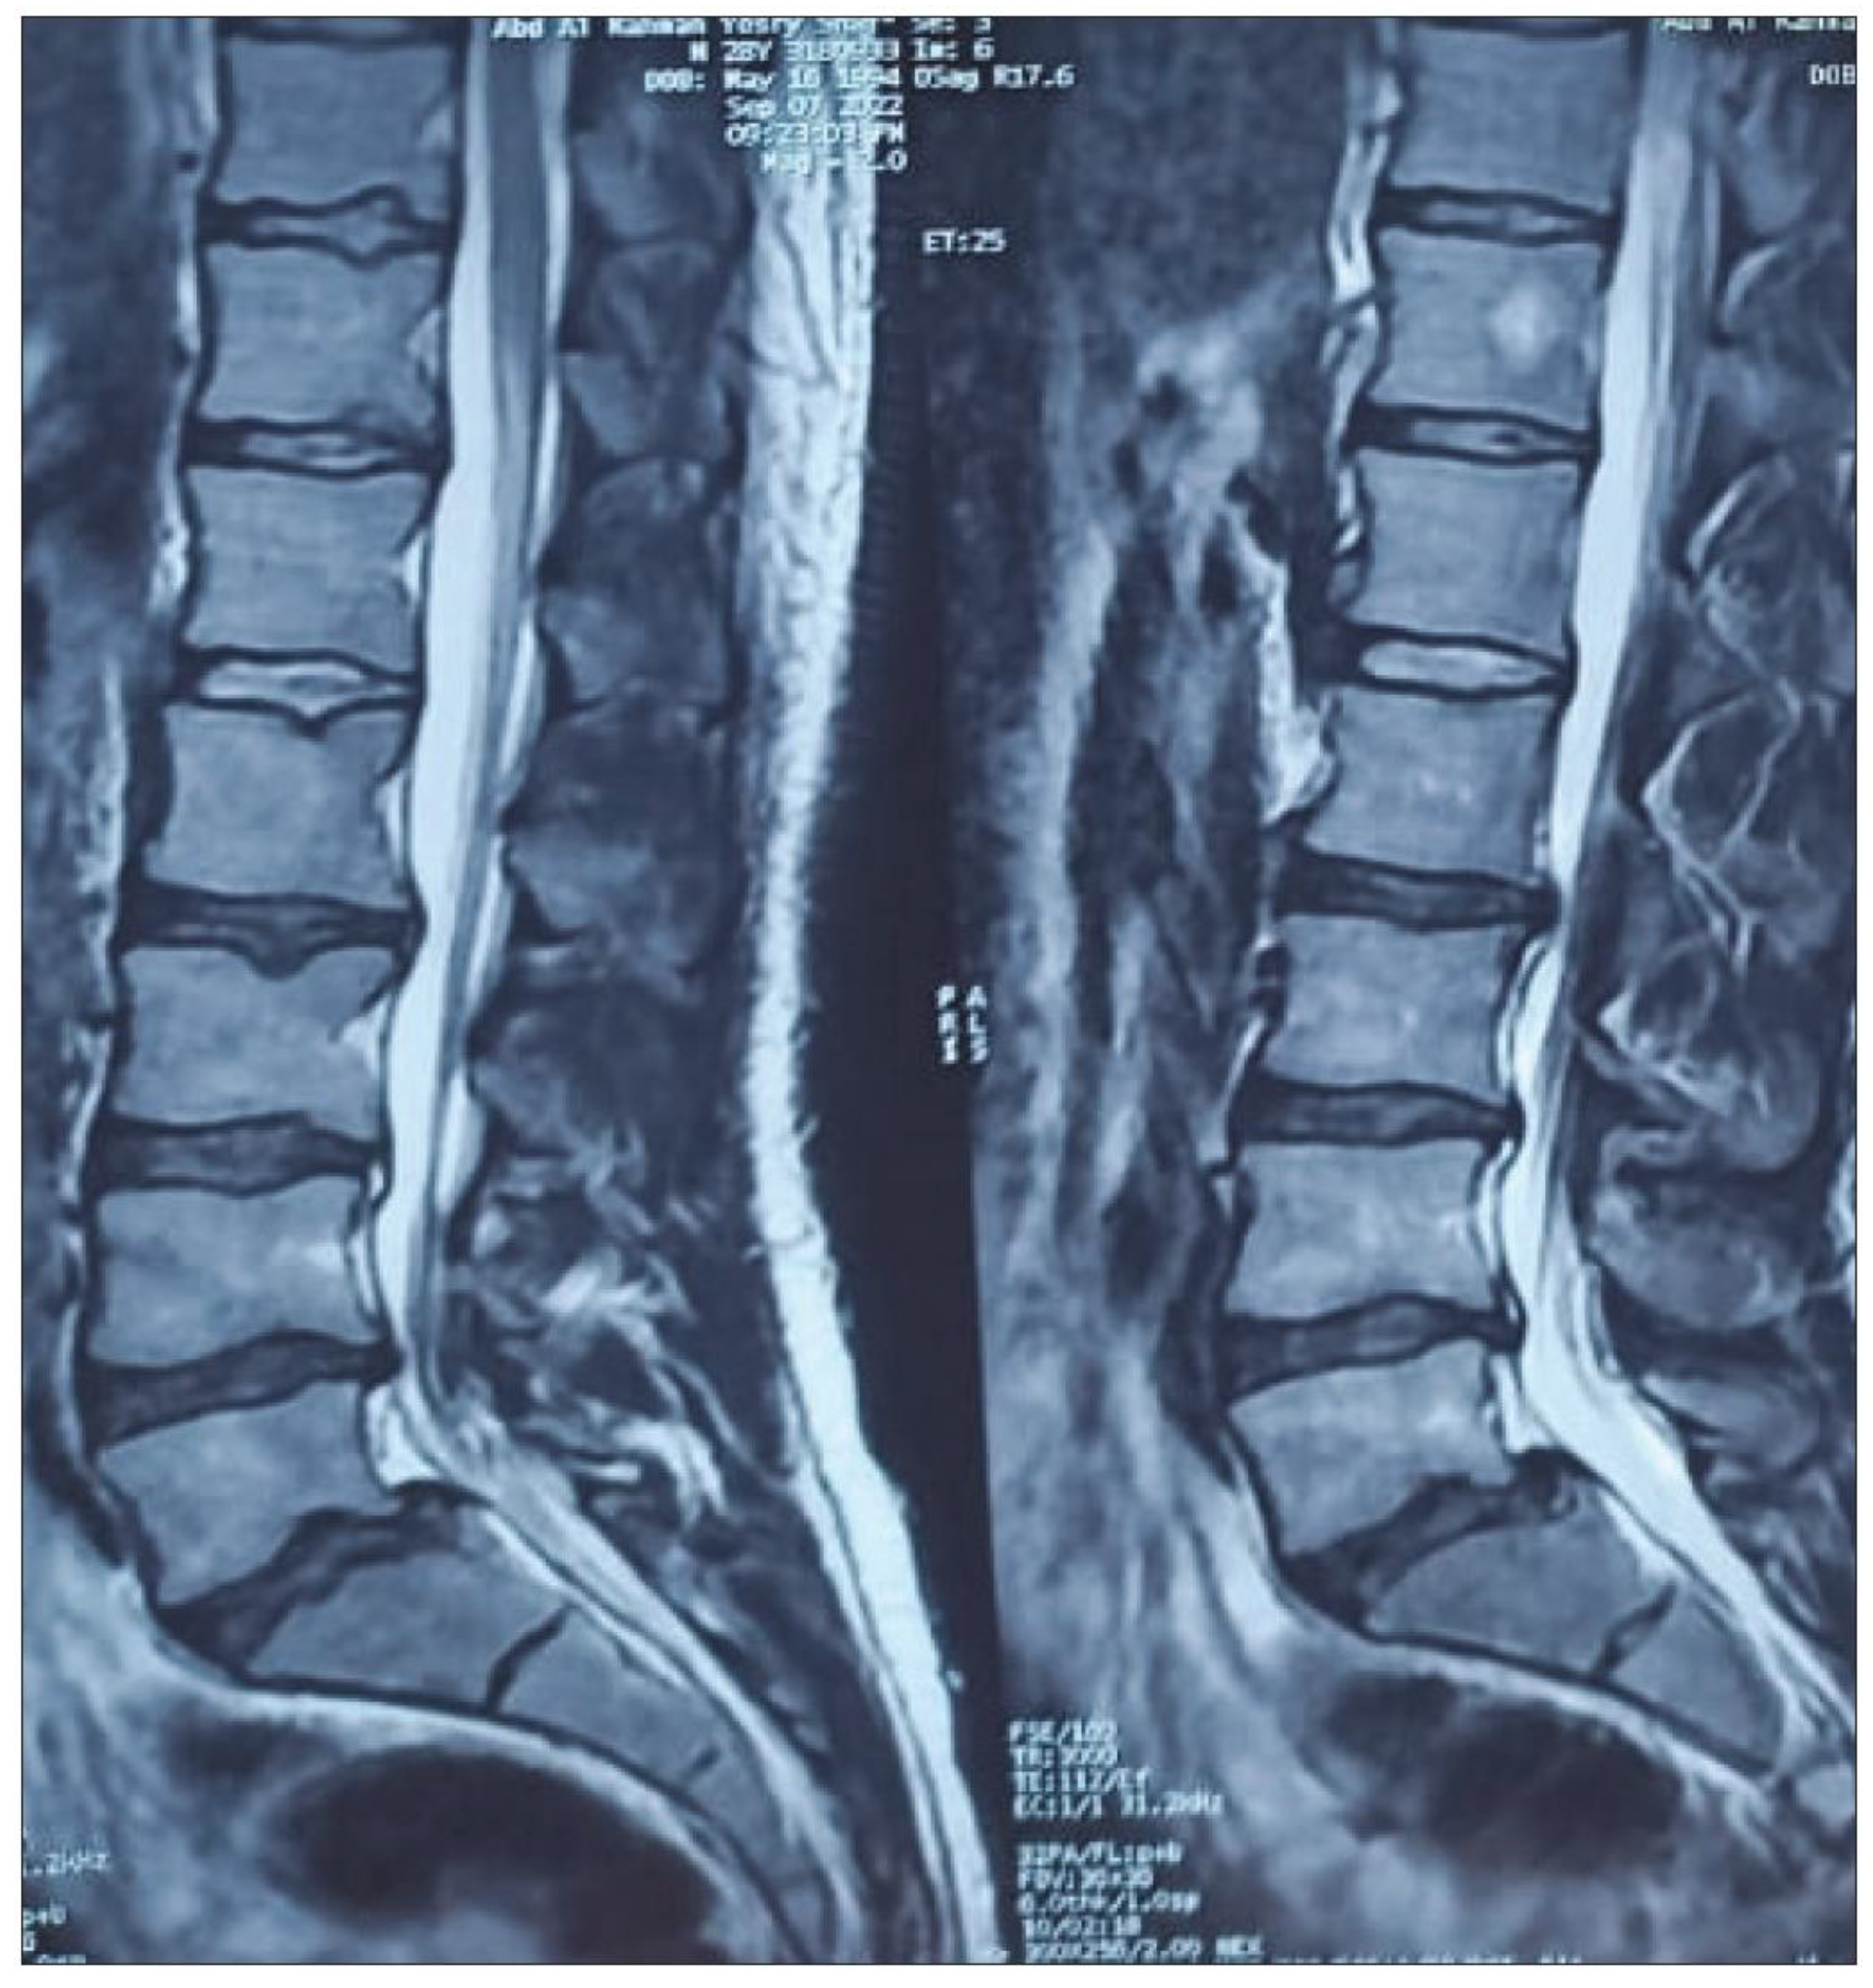

- Mysliwiec LW, Cholewicki J, Winkelpleck MD, Eis GP. MSU classification for herniated lumbar discs on MRI: toward developing objective criteria for surgical selection. Eur Spine J. 2010;19:1087–93. [CrossRef]